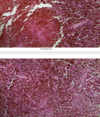

Diagnose Describe Arrows

Chronic venous congestion of liver Central veins and sinusoids are dilated and congested, Liver cells in periphery show cloudy swelling and fatty degeneration Blue: portal tract Black: congested centeral vein